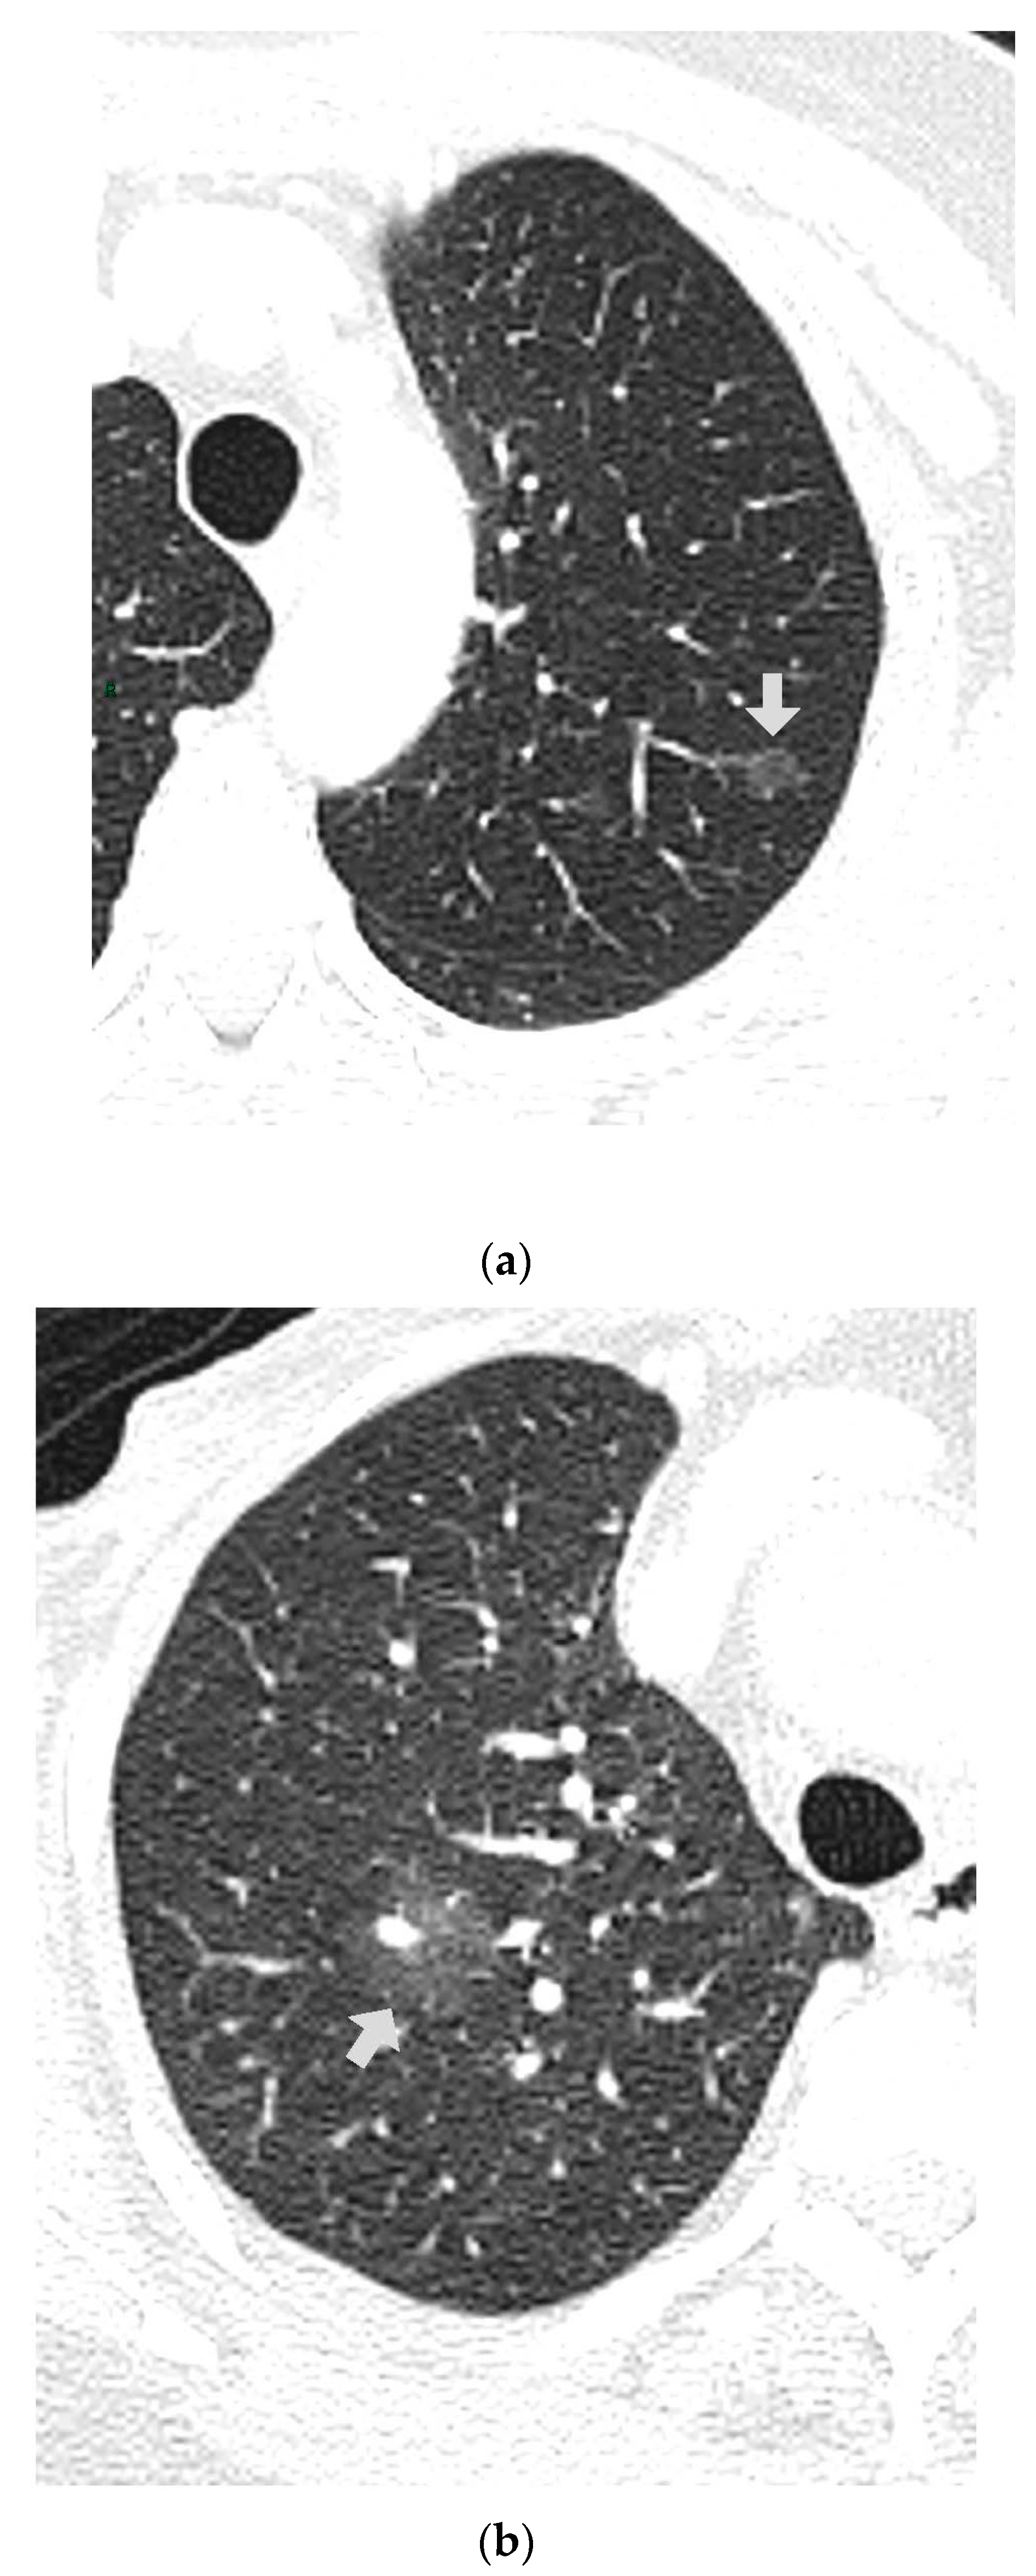

CT images were analyzed for the presence of SSNs and their features (number, size, distribution by lobes, number of involved lobes, and solid components). SSNs were classified into pure ground glass, heterogenous ground glass, and part-solid nodules based on their attenuation on CT images and measurable soft tissue components [5] (Figure 1, Figure 2 and Figure 3).

Figure 2. (a,b) Two heterogenous GGNs in different patients; RLL and RUL.